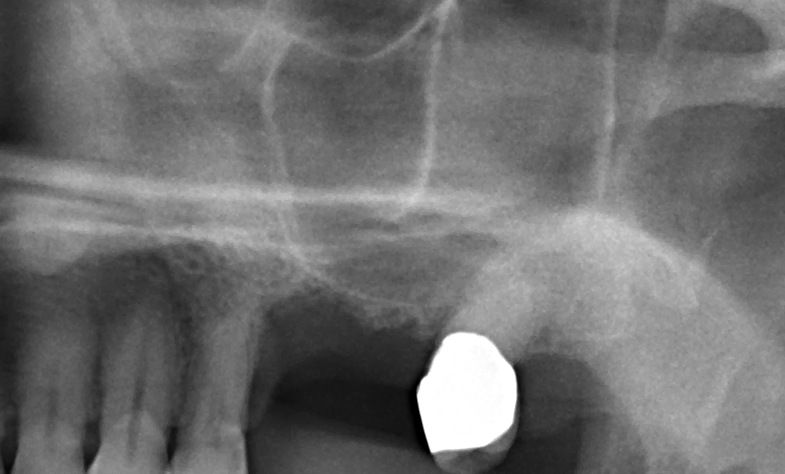

Bildgebende Verfahren im Vergleich. Was Sie aus forensischen Gründen nicht nur für die Implantologie unbedingt wissen müssen.Ein trockenes Thema spannend aufbereitet.